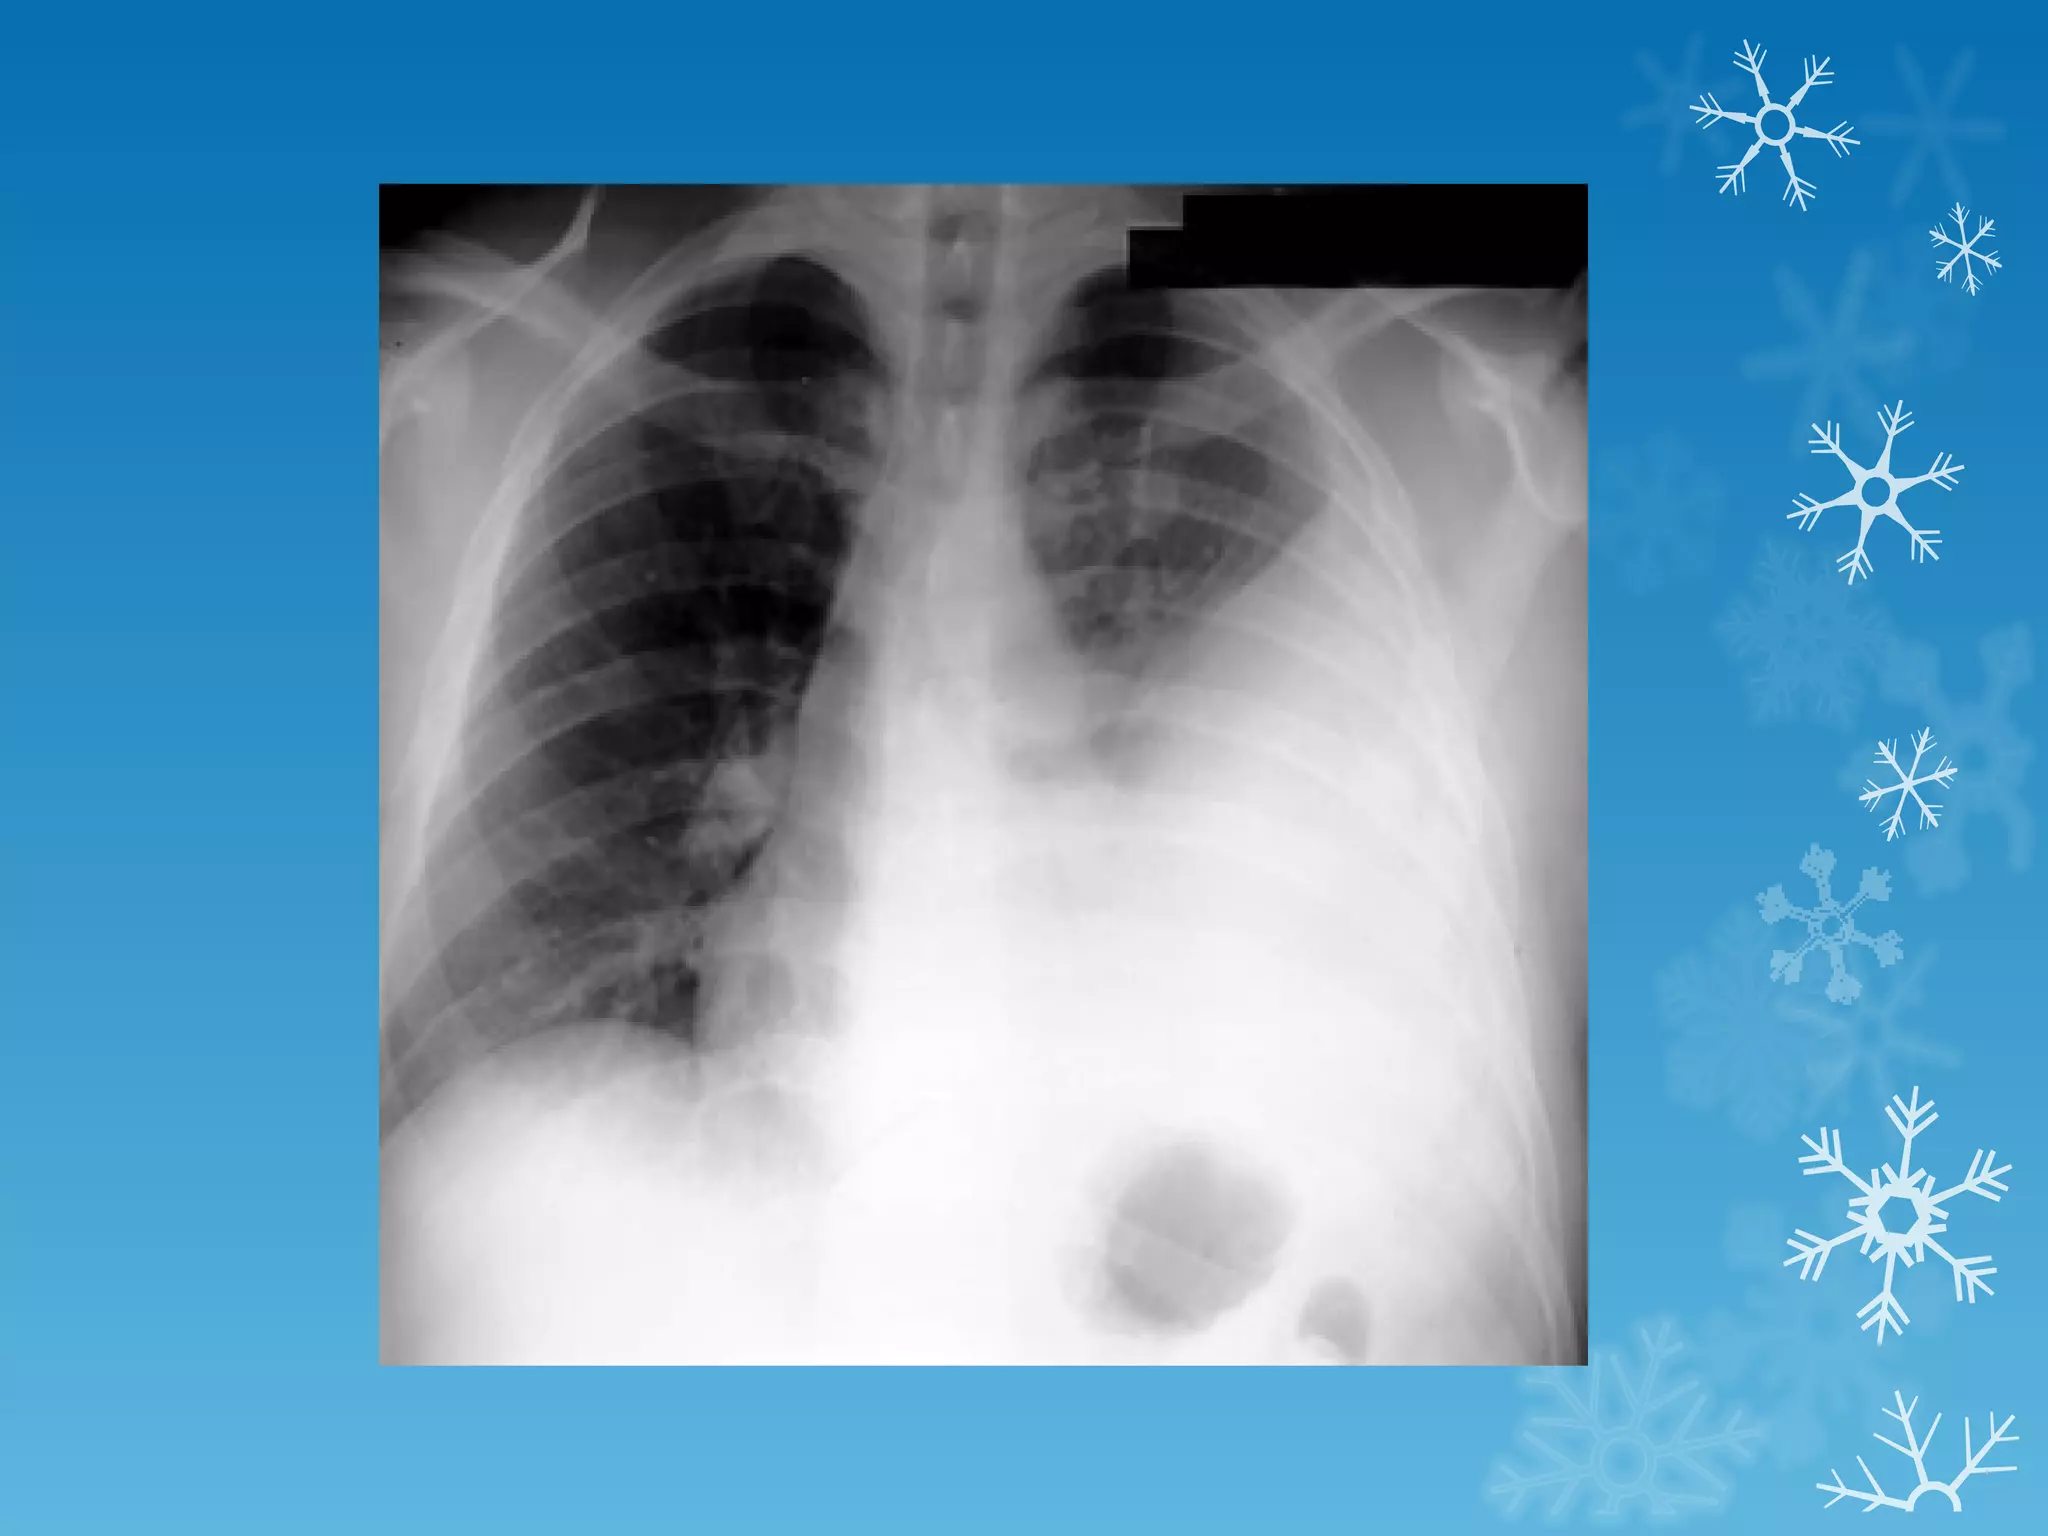

This document discusses chest x-ray interpretation and provides guidance on evaluating x-rays. It explains that tissue density determines how an x-ray beam penetrates, with denser tissues appearing whiter and less dense tissues appearing blacker. It also outlines different chest x-ray views and factors to consider like patient orientation, age, gender, and rotation. Abnormalities are described as appearing too white, too black, too large, or in the wrong place. The document stresses a systematic approach of identifying, localizing, describing lesions, and providing differential diagnoses.